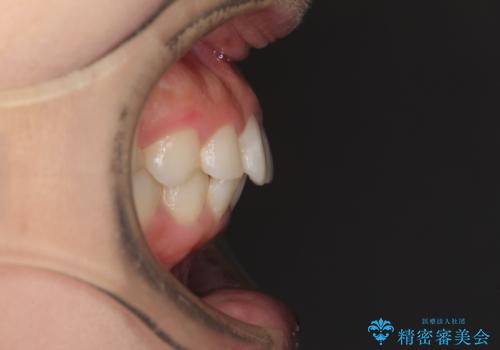

- 以前の矯正治療の後戻りを気にして来院された患者様です。

下顎前歯にデコボコがあるため、ワイヤー矯正により改善することとしました。